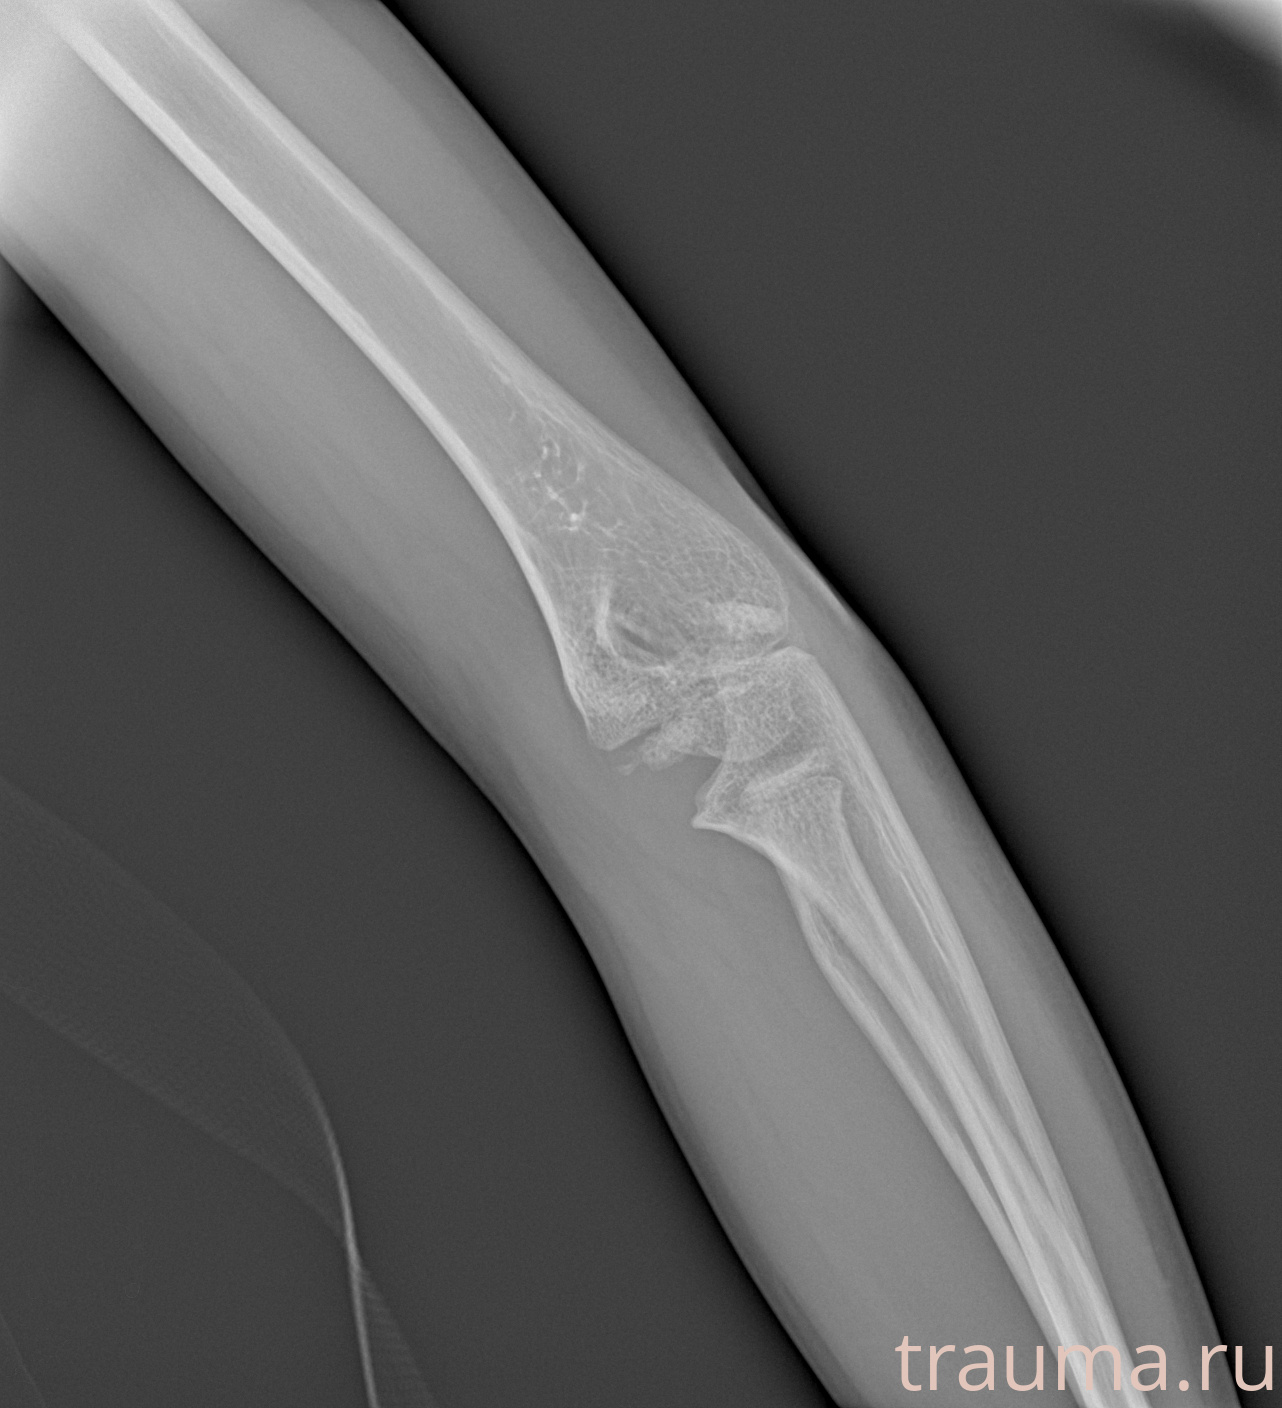

Рентгенограммы

Рентген на дому: по вашему адресу приезжает врач-рентгенолог, травматолог-ортопед с мобильным рентгеновским аппаратом, проводит диагностику травмы или заболевания, делает необходимые рентгенограммы, дает рекомендации по дальнейшему лечению. Получить качественные снимки в домашних условиях возможно благодаря уникальной методике, разработанной МосРентген Центром для института  Склифосовского